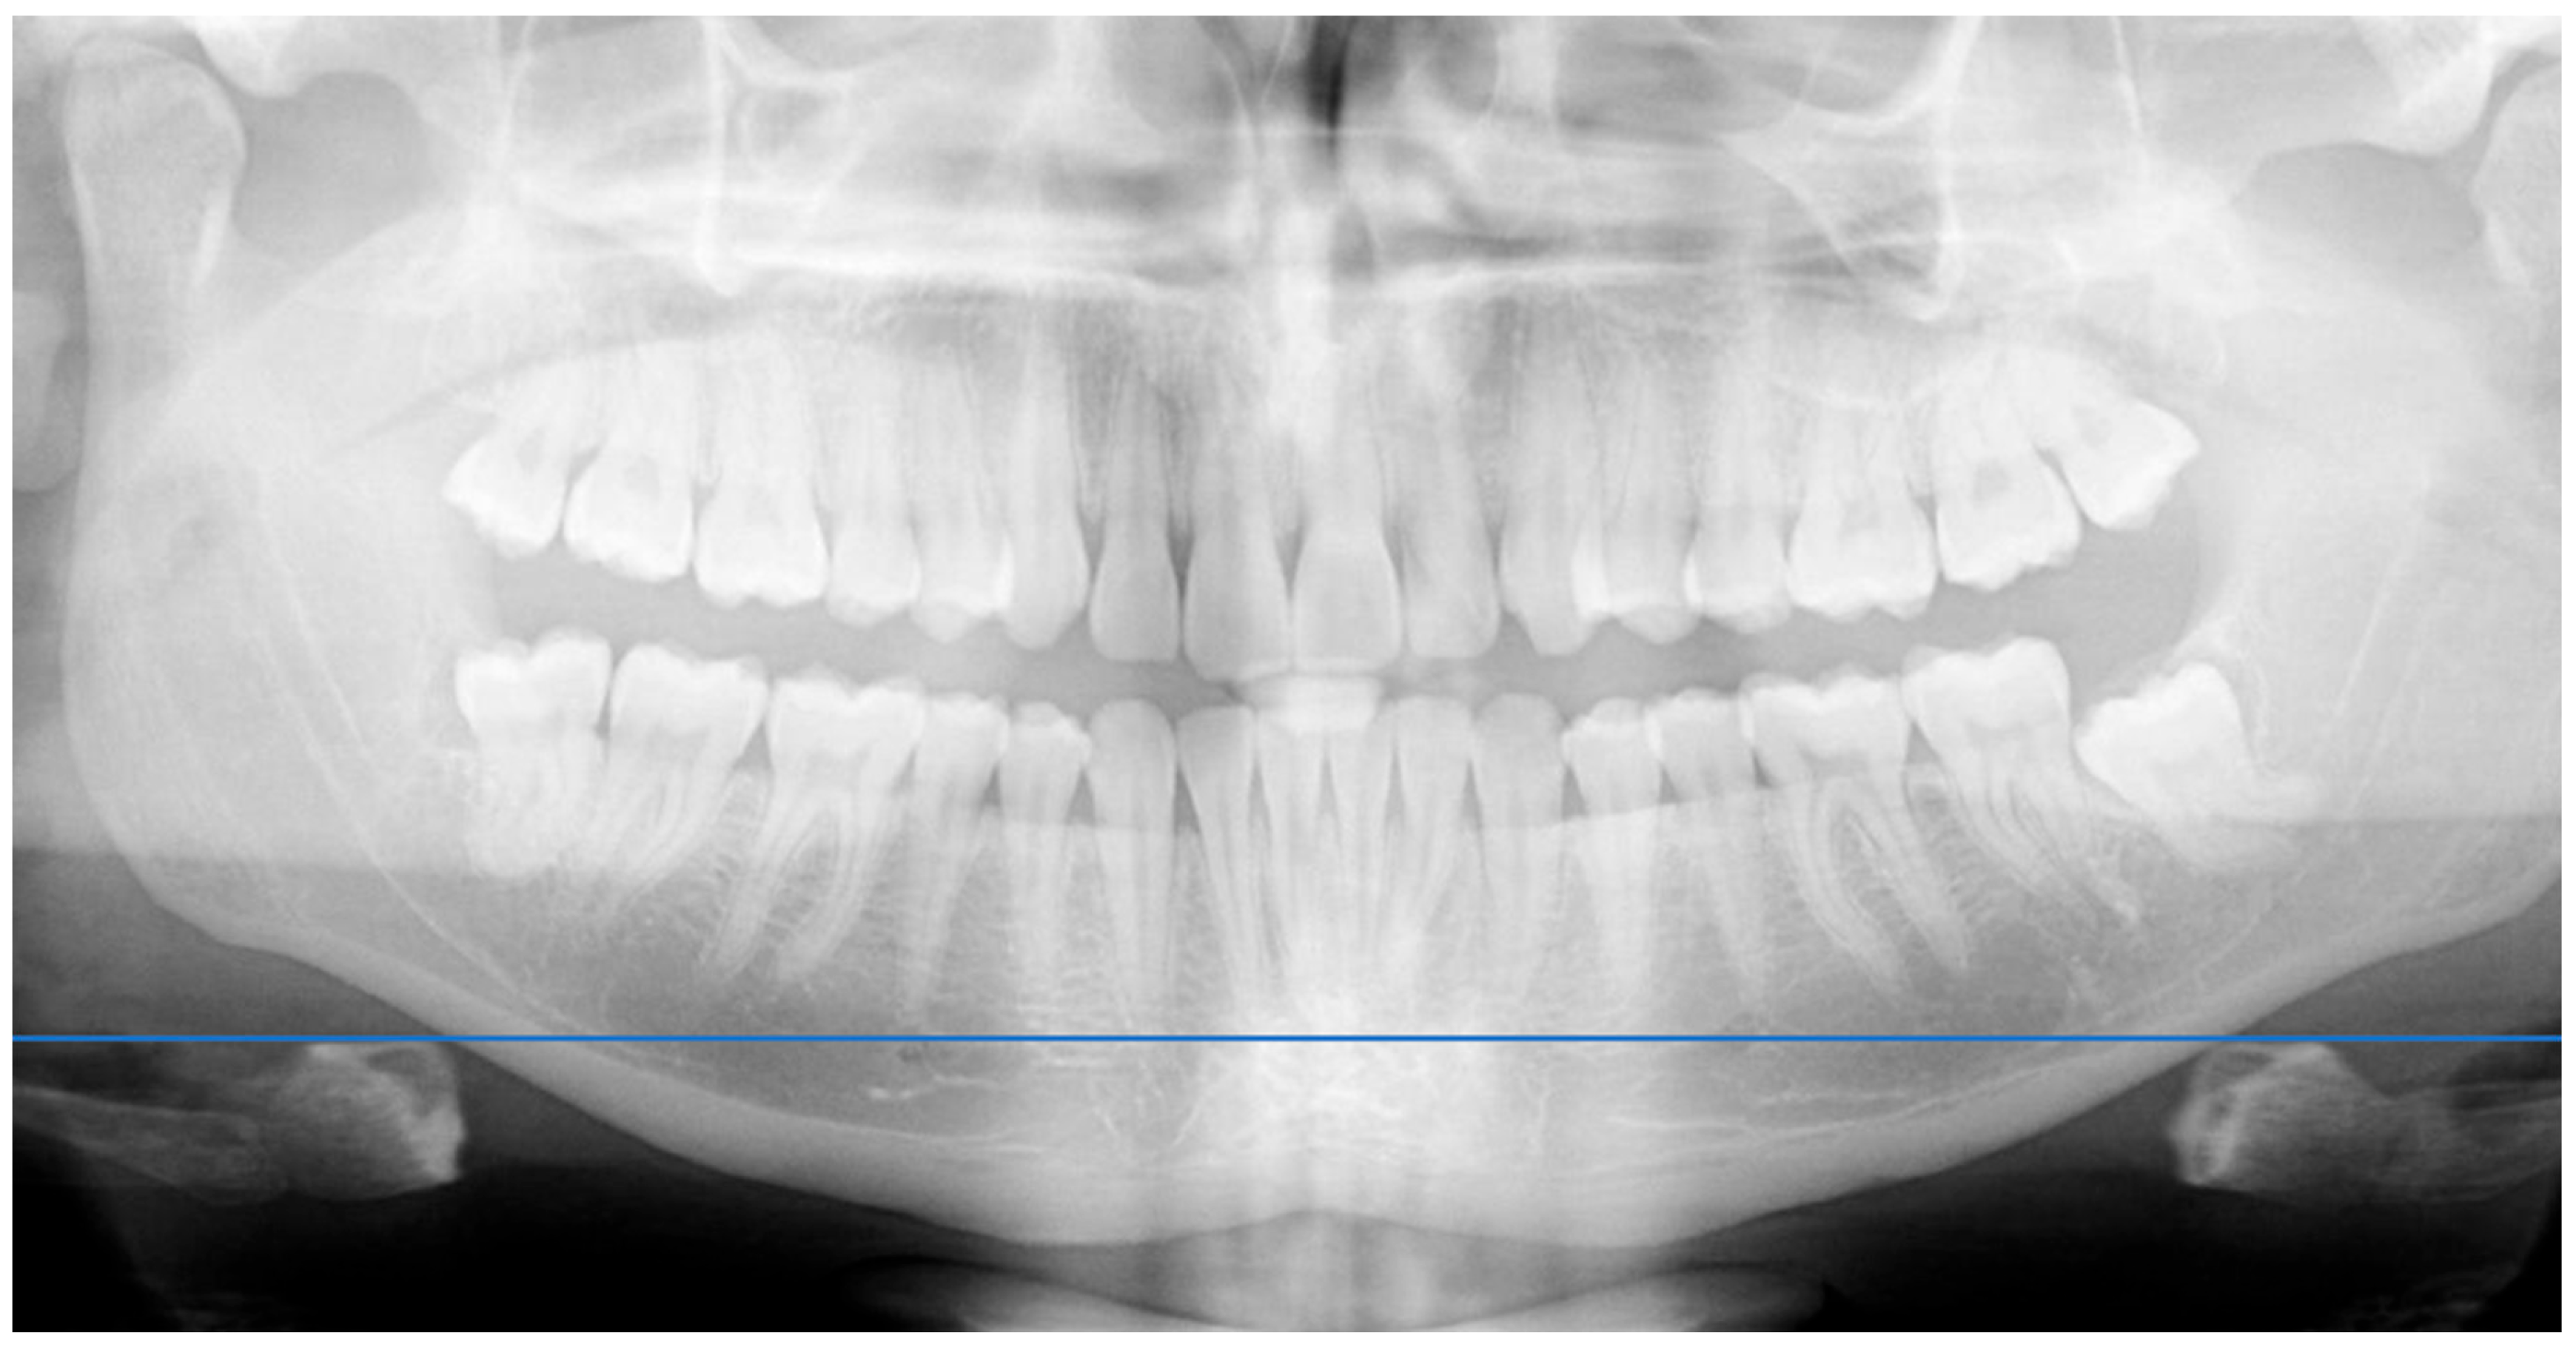

Figure 1. (A): Right-side AFMP measured using a protractor overlay. (B): Left-side AFMP measured using a protractor overlay. - Radiographic Analysis: A panoramic radiograph was obtained for each participant. A horizontal line was drawn across the hyoid bone, and vertical distances were measured from the upper border of the hyoid to the antegonial notch on each side using a digital ruler overlay (Figure 2). Distances were measured digitally from the most superior point of the hyoid body to the antegonial notch bilaterally, using an on-screen ruler calibrated at the same scale.

Figure 2. Horizontal reference line drawn for comparative analysis of hyoid bone position.

Image quality and positioning control. All radiographs followed standardized acquisition protocols. To minimize image distortion, patient posture, head alignment, and tongue position were carefully controlled. The operator followed manufacturer recommendations and ensured alignment with anatomical planes (sagittal and Frankfort). Proper positioning was critical to avoid magnification errors, especially in younger patients [14,15,16]. Operator experience and patient cooperation were emphasized, as involuntary movements or incorrect tongue position are known to produce magnification and ghost-image artifacts in panoramic radiography.